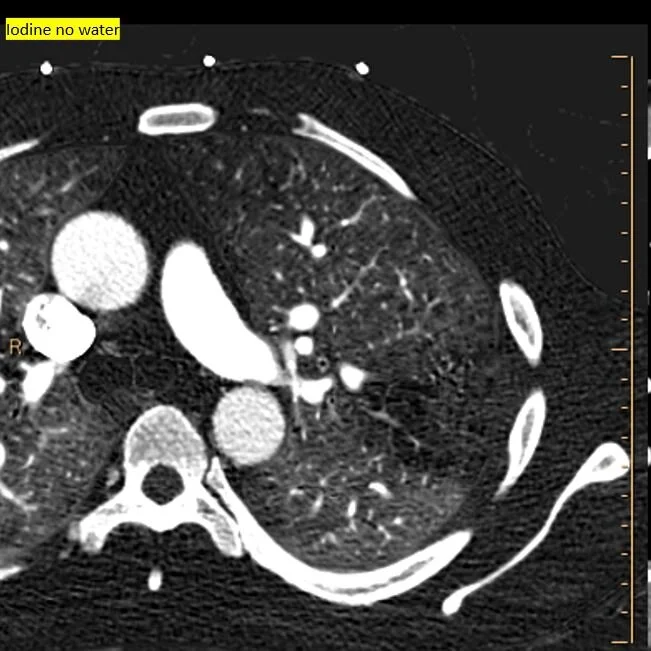

Iodine map shows focal nodule of uptake in the pleural thickening

40 keV monoE: Nicely depicts the aneurysm!

A few days prior to the massive hemothorax, he presented with pleuritic chest pain. CXR showed a small pleural effusion. On conventional CT, there is a small area of pleural thickening in the left upper lobe, near the previous infarct. On Spectral CT, a small aneurysm is clearly visible on the 40 keV image and iodine map. This is what bled a few days later.